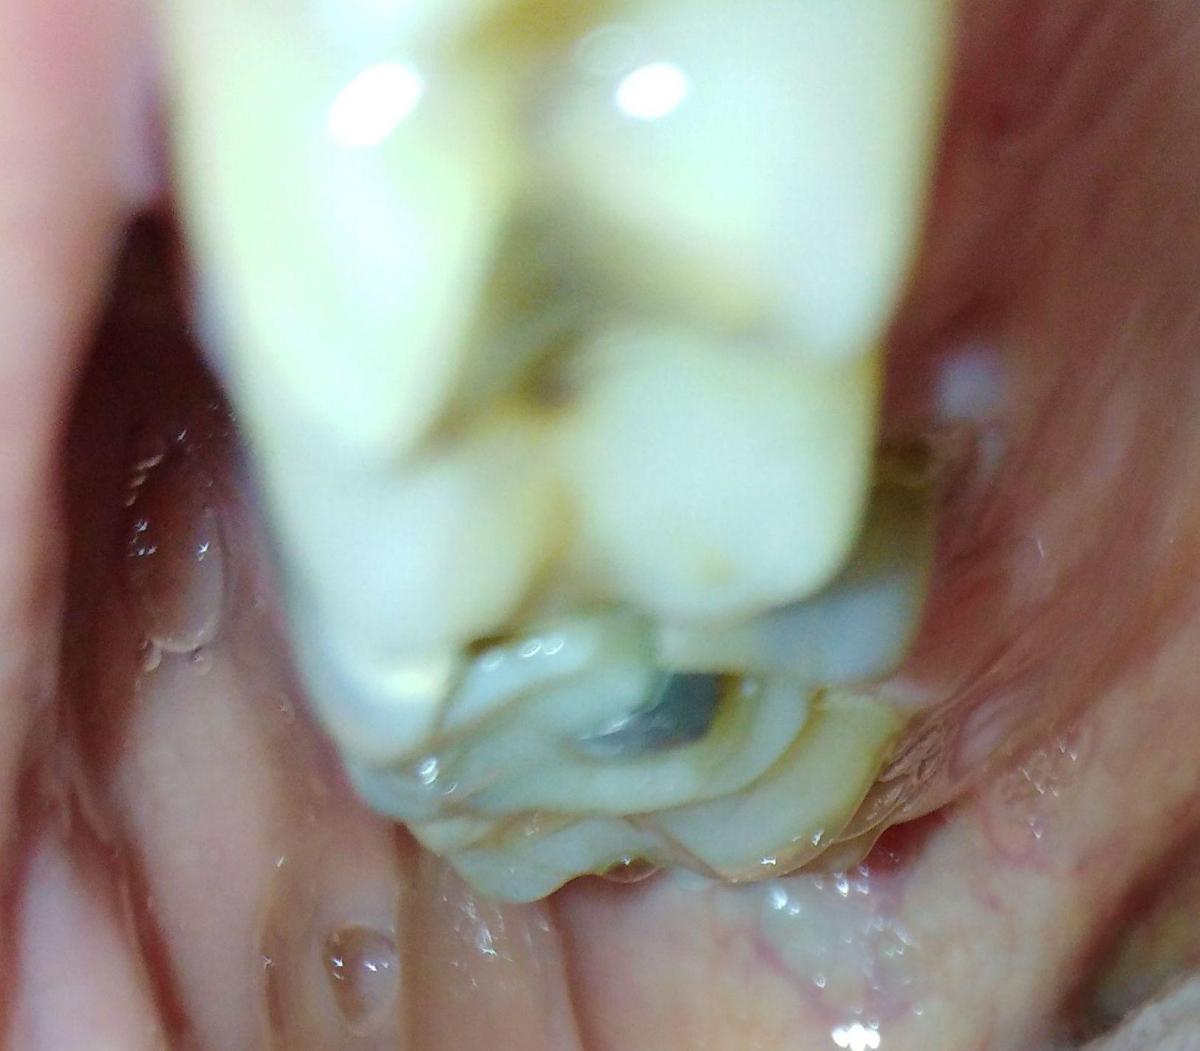

Интересовала в частности развалившаяся 6-ка сверху.

уже давно леченная -перелеченная.

По поводу 6 ки я еще готов удалить так как там похоже невозможно что-то сделать но 4-ка с 5-кой свиду не такие плохие. возможно их перелечить ?

6-ку я так понимаю все-равно лучше удалить ? у меня такая же на другой стороне там тоже огромная пломба со штифтом

вот уже лет 10 и пока стоит. Если вычистить и опять сделать пломбу ( понятно что коронке не на чем держаться.)